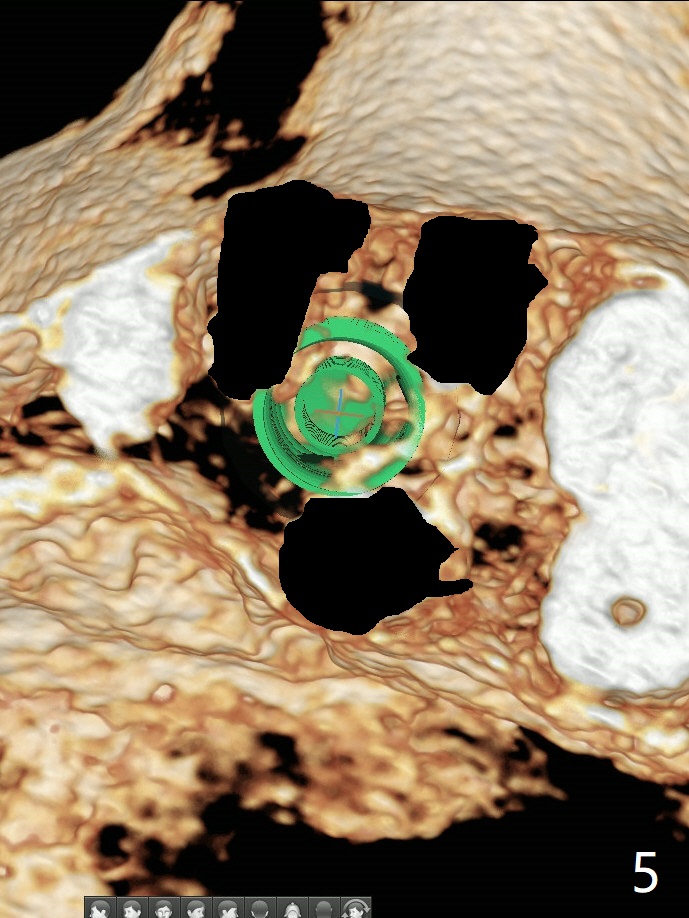

44岁女左上6远中深龋(图一:*),同意拔除种植(图二),由于近中,远中牙槽嵴不等(*),为了增加冠根比例,植体可以种浅些(箭头),但是远中多放置骨粉(红色)。为了防止钻头偏移中隔,去除牙冠(图三),保留牙根情况下,完成钻洞(图四:红色),然后拔除牙根(图五:黑色),放置植体(绿色)。